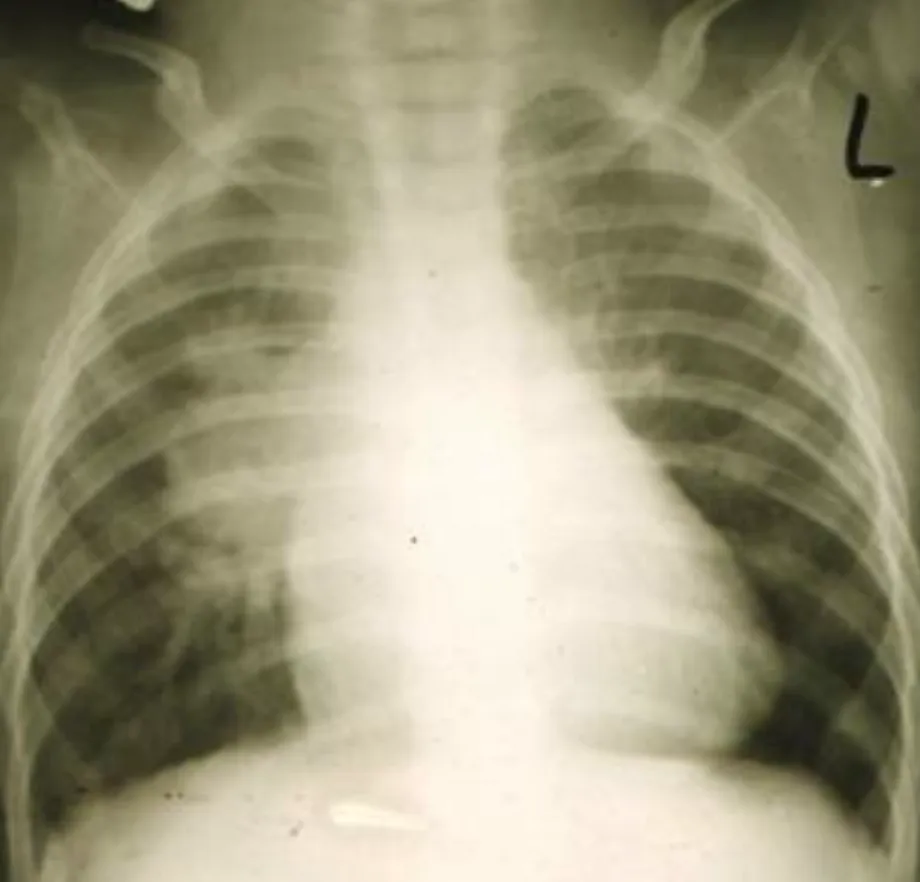

【111-2 醫學(四) 第30題】

一位 6 個月大男嬰因呼吸急促就醫,身體診察時在左胸前可聽到第三度 to-and-fro 心雜音,於右肋下緣 4 公分可觸摸到肝臟腫大,胸部 X 光如圖所示。下列何者為最可能的診斷?

破題關鍵

這題的關鍵在於結合臨床症狀「呼吸急促」、「to-and-fro 心雜音」、「肝臟腫大」以及胸部X光片上「心臟明顯擴大」和「肺動脈段異常突出」的特徵,指向先天性肺動脈瓣膜缺失症合併心室中隔缺損。